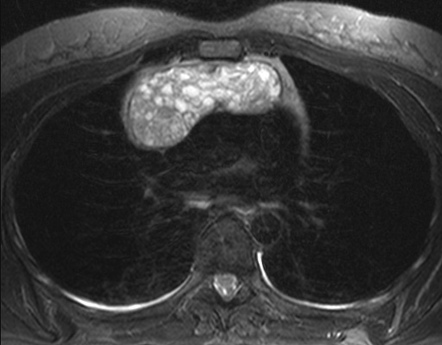

На Т1-взвешенных изображениях определяется гипоинтенсивное или изоинтенсивное объёмное образование в переднем средостении с ровными или умеренно неровными контурами.

На Т2-взвешенных изображениях визуализируется гиперинтенсивная структура опухоли, иногда с неоднородностью сигнала при наличии кистозных или некротических изменений.

На изображениях с подавлением сигнала от жира подчёркивается разграничение тимомы от окружающей клетчатки и прилежащих сосудистых структур, что облегчает определение её распространённости.

В режиме с подавлением сигнала от воды фиксируются зоны неоднородности внутри опухоли, свидетельствующие о наличии фиброзных компонентов или кровоизлияний.

В режиме динамического контрастного усиления определяется умеренное или выраженное накопление контраста опухолевой тканью, что отражает её васкуляризацию и позволяет уточнить жизнеспособность опухоли.

В режиме трёхмерной реконструкции визуализируются размеры, объём и степень инвазии тимомы в соседние структуры средостения, включая перикард, плевру и сосуды.